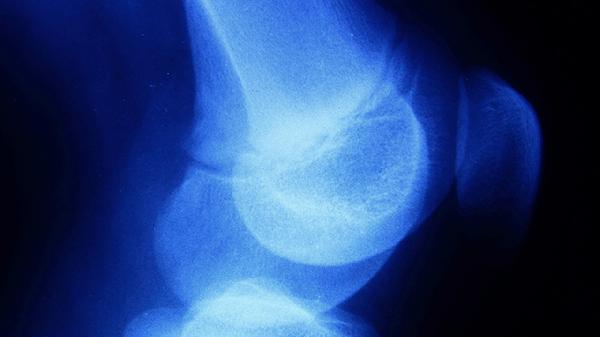

睾酮和生长激素协同促进骨骼纵向生长,青春期后期雌激素水平上升会加速生长板闭合。性早熟患者因激素异常可能导致12-14岁即完成闭合,而垂体功能减退者可能延迟至20岁后。

慢性肾病、炎症性肠病等消耗性疾病可能延迟闭合2-3年,这类患者常伴随体重偏低、第二性征发育迟缓。甲状腺功能亢进则可能使闭合年龄提前,需监测骨龄进展速度。

建议定期监测身高增长速度,青春期男孩每年应进行至少一次骨龄评估。保证每日摄入含钙食物如奶酪、豆腐,配合户外活动促进维生素D合成。避免过度节食或使用蛋白粉等补剂,发现年生长速度低于4厘米或出现性征发育异常时需及时就诊内分泌科。睡眠时间建议不少于8小时,深度睡眠阶段生长激素分泌量可达清醒时的3倍。